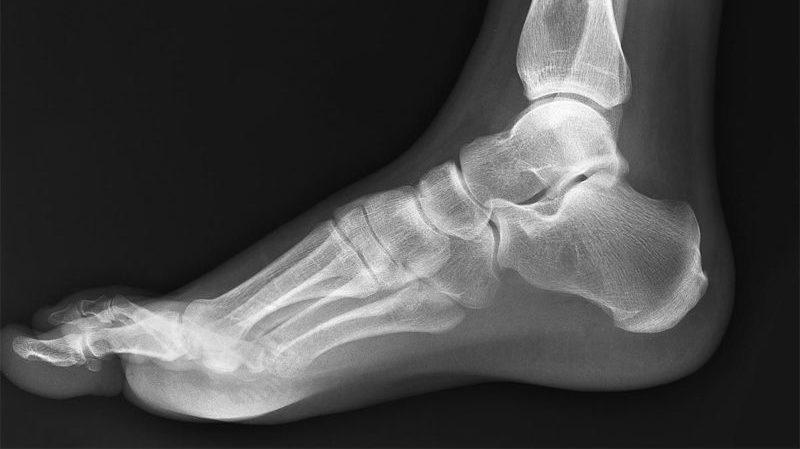

Плоскостопие – достаточно распространенная проблема как у детей, так и у взрослых. Такая патология создает человеку дискомфорт, доставляет болезненные ощущения. Иногда, например, на 1-й стадии, хватает консервативного лечения, чтобы избавиться от данного заболевания. Но на 2-3 стадиях болезни чаще всего требуется оперативное вмешательство, чтобы привести в норму свод стопы.

Такой период продолжается примерно две недели. Затем врач назначает рентген, меняет гипс. Пациенту разрешается передвижение на костылях. Через 6 недель, после повторного рентгена, снимают гипс. Пациент получает специфическую стельку для того, чтобы носить ее в обуви. Это должна быть удобная, правильно подобранная обувь без каблука.